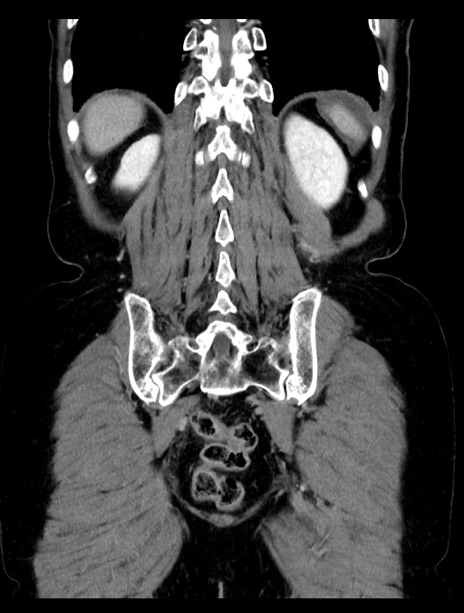

症例23(冠状断像)

【症例】70歳代女性

【主訴】下腹部痛・嘔吐

【現病歴】2日前より腹痛あり。昨日嘔吐あり。症状改善しないため来院。

【既往歴】胃GISTに対して胃部分切除後。

【身体所見】BT 37.1℃、BP 128/77mmHg、腹部:平坦・軟、下腹部に圧痛あり。

【データ】WBC 10200、CRP 0.31